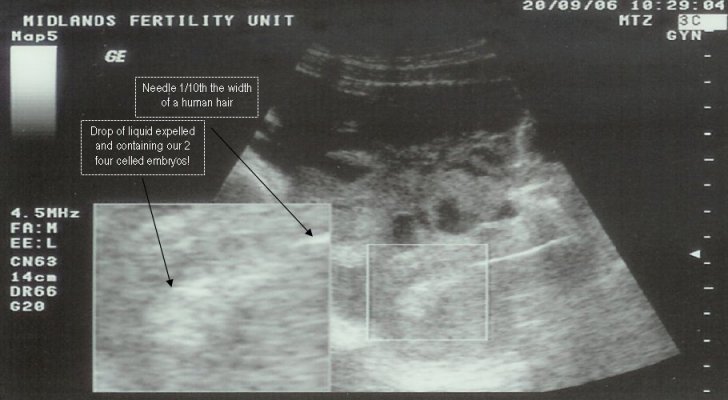

Photo - ICSI2